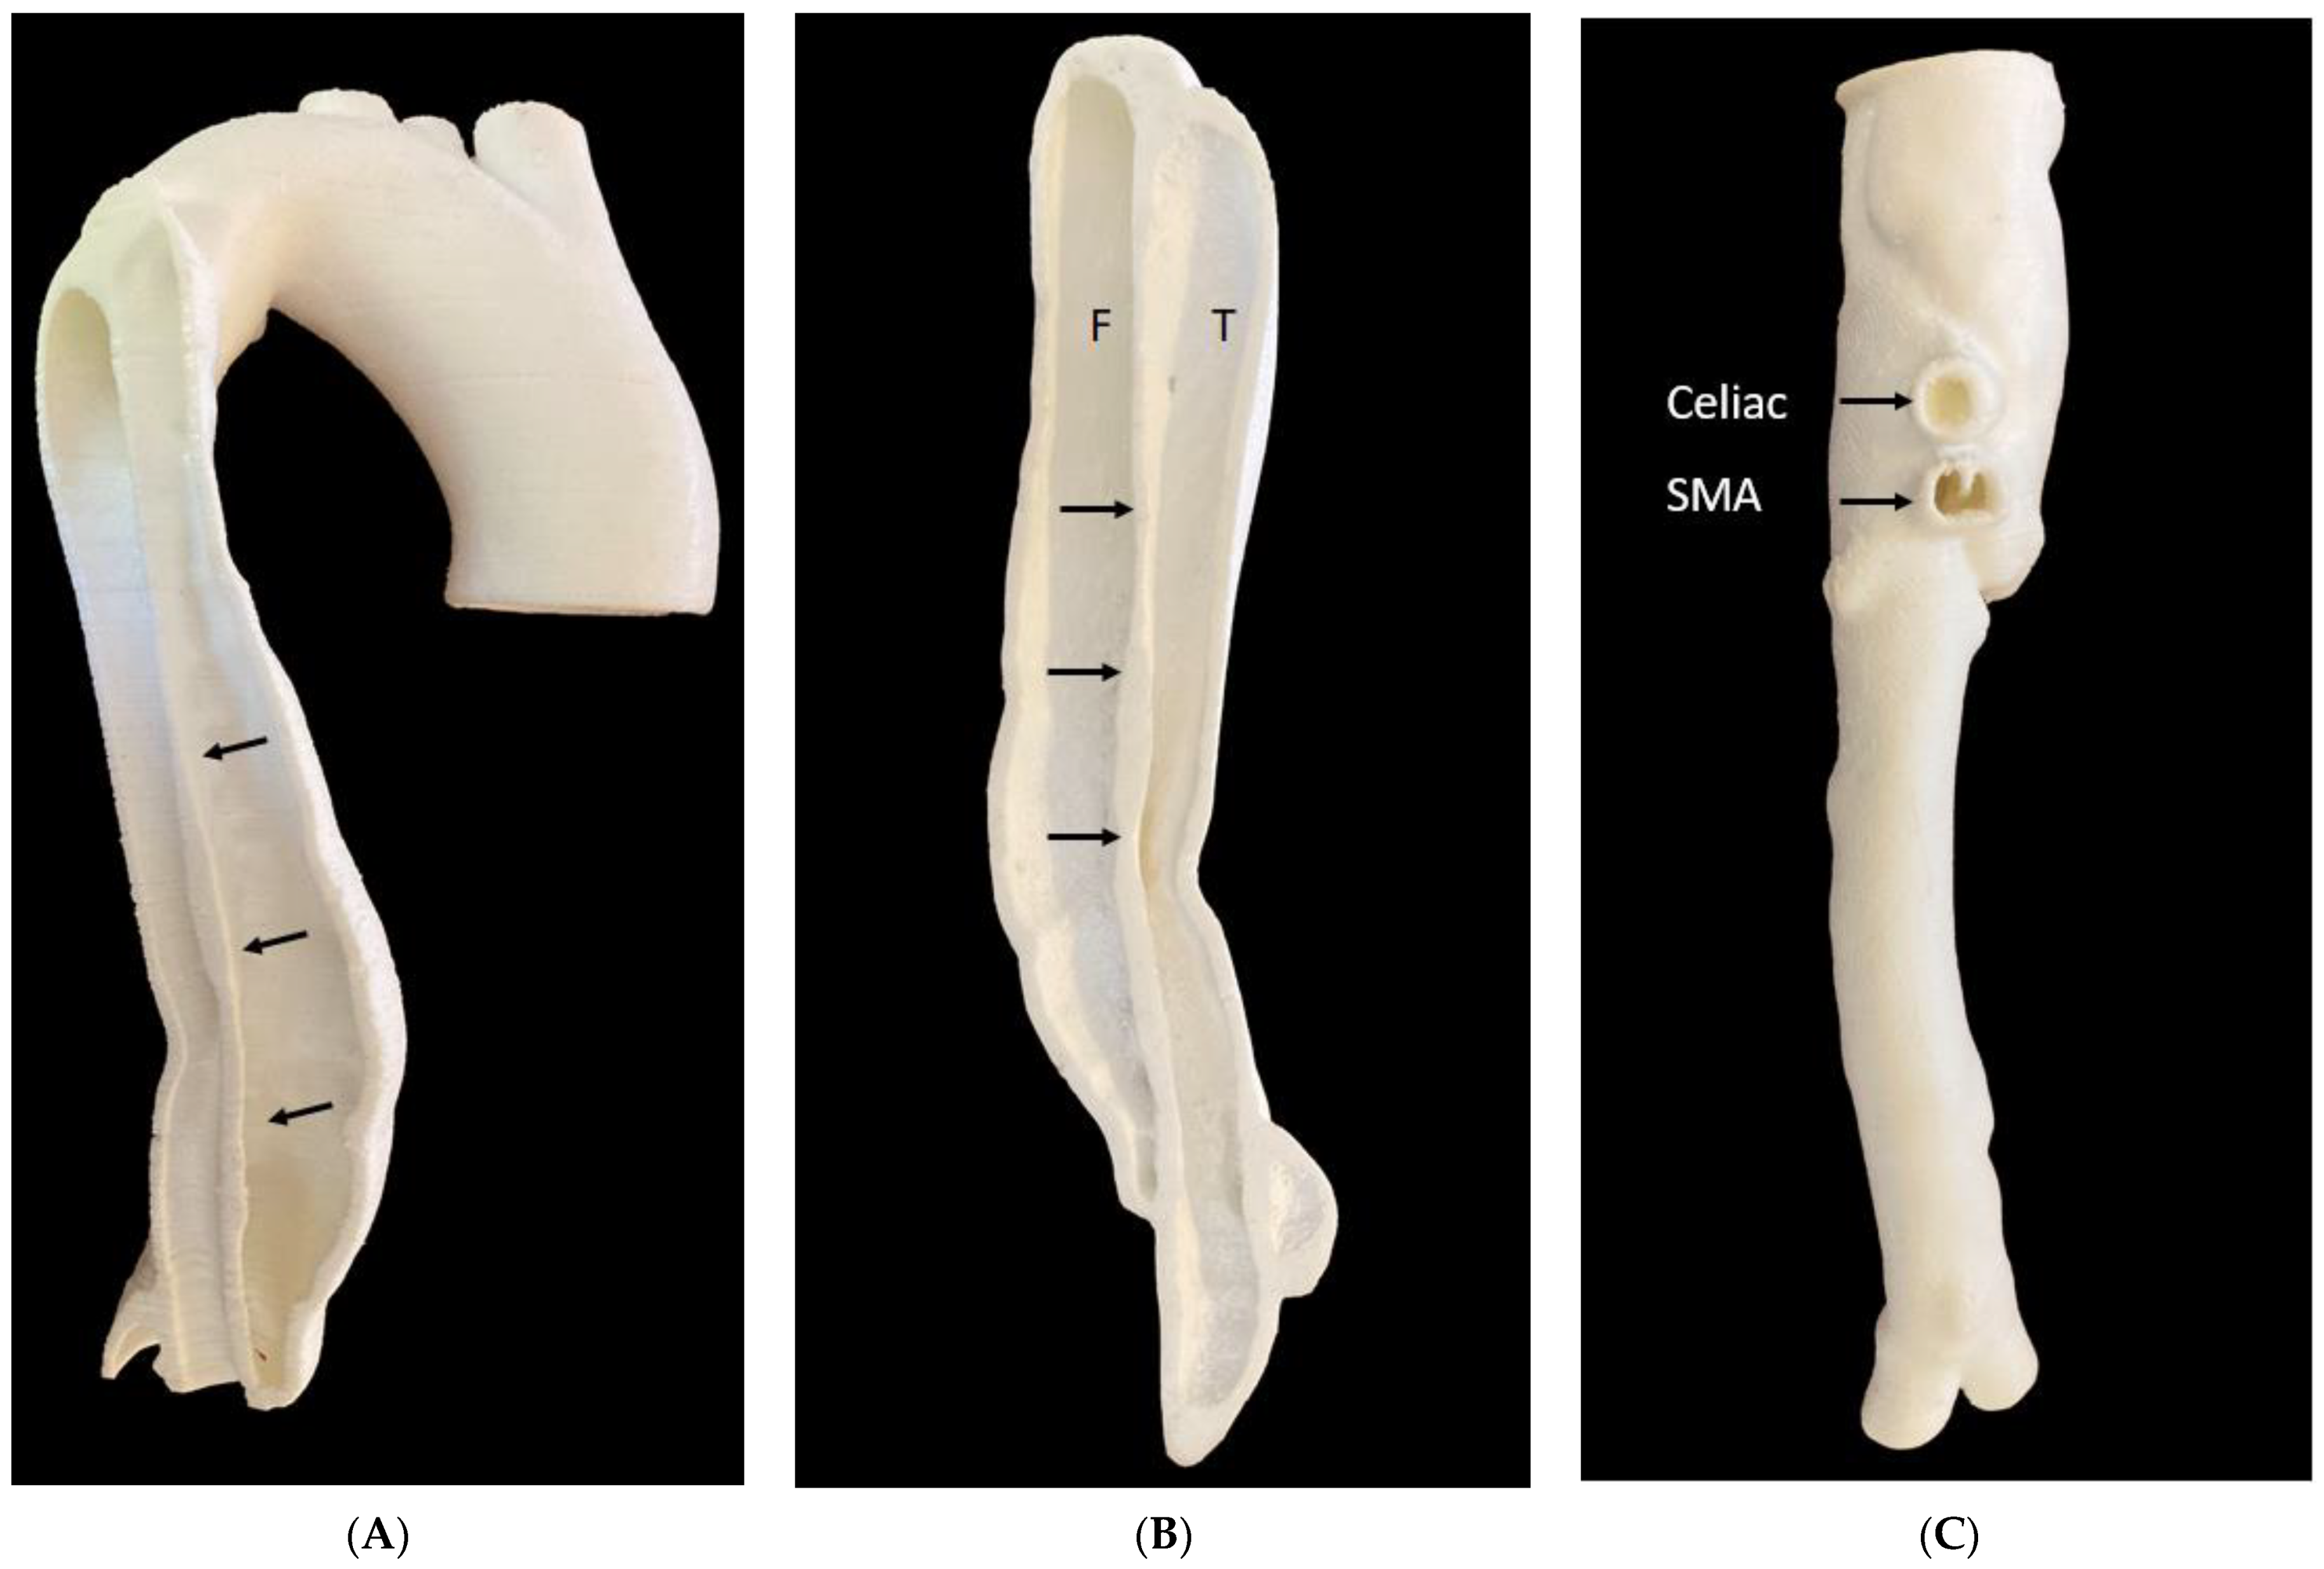

4.5. 3D-Printed Aorta Models

- Torres, I.O.; De Luccia, N. A simulator for training in endovascular aneurysm repair: The use of three dimensional printers. Eur. J. Vasc. Endovasc. Surg. 2017, 54, 247–253. [Google Scholar] [CrossRef] [Green Version]

- Karkkainen, J.M.; Sandri, G.; Tenorio, E.R.; Alexander, A.; Bjellum, K.; Matsumoto, J.; Morris, J.; Mendes, B.C.; DeMartino, R.R.; Oderich, G.S. Simulation of endovascular aortic repair using 3D printed abdominal aortic aneurysm model and fluid pump. Cardiovasc. Intervent. Radiol. 2019, 42, 1627–1634. [Google Scholar] [CrossRef]

- Kaufmann, R.; Zech, C.J.; Takes, M.; Brantner, P.; Thieringer, F.; Dentschmann, M.; Hergan, K.; Scharinger, B.; Hecht, S.; Rezar, R.; et al. Vascular 3D printing with a novel biological tissue mimicking resin for patient-specific procedure simulations in interventional radiology: A feasibility study. J. Digit. Imaging 2022, 35, 9–20. [Google Scholar] [CrossRef]

- Wu, C.; Squelch, A.; Sun, Z. Investigation of three-dimensional printing materials for printing aorta model replicating type B aortic dissection. Curr. Med. Imaging 2021, 17, 843–849. [Google Scholar] [CrossRef] [PubMed]

- Wu, C.; Squelch, A.; Sun, Z. Assessment of optimization of computed tomography angiography protocols for follow-up type B aortic dissection patients by using a 3D-printed model. J. 3D Print. Med. 2022, 6, 117–127. [Google Scholar] [CrossRef]

| Aorta | 6: Abdominal aortic aneurysm: 5 Aortic dissection: 1 | CT | Aortic aneurysm and aortic dissection for the simulation of endovascular repair and CT protocols | Printer: Ultimaker 2+ Extended/Raise3D N2 Plus Materials: Thermoplastic polyurethane (TPU) 95A, PLA, polyethylene terephthalate glycol (PETG), polymethacrylate (PMMA) and high impact polystyrene (HIPS) Cost: USD 50 per model | Aorta was printed with PLA, HIPS, PMMA were at a resolution of 12.5 μm for the x, y and z-axis planes. Aorta was printed with TPU95A was at a resolution of 12.5 μm for the x and y-axis planes; 10 μm for z-axis plane Time: ~100 h per model |